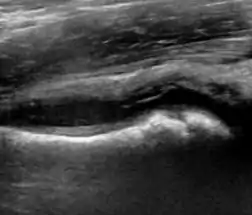

Ultrasound

Ultrasound is the first-choice technique for diagnosis of newborns hip dysplasia. In experienced hands with appropriate technology, ultrasound can also be useful during the first year of life. Some European healthcare systems encourage universal ultrasound screening in neonates between the sixth and eighth weeks. Although it shows higher initial costs caused, it leads to significant reduction in the total number and overall costs of dysplastic hips undergoing operative and nonoperative treatment.[1]

Ultrasound allows categorizing pediatric hips, according to Graf’s criteria, in four main types: normal, immature, and dysplastic (subluxed and dislocated). This classification is based on measurements of the acetabular inclination angle (alpha), cartilage roof angle (beta), and infant age. The femoral head coverage can also be determined by dividing the length of the femoral head covered by the acetabular fossa and the diameter of the femoral head. Its lower normal limits are 47% for boys and 44% for girls (Figure 11).[1]

Figure 11:

Useful ultrasound measures in neonatal hip sonography, alpha and beta angles.[1]

Measurement of femoral head coverage.[1]

During childhood, ultrasound is a quick method to assess hip pain and quite often may be used to avoid use of irradiating techniques, such as radiography or CT. Ultrasound allows evaluation of joint effusion, synovial thickening and neovascularity, the bone/cartilage contour, and the femoral head-neck alignment. Although sonography is extremely sensitive in detecting increased synovial fluid, it is nonspecific and cannot be used with accuracy to determine the type of fluid. Transient synovitis of the hip, despite being the most frequent cause of pain in children between 3 and 10 years, remains a diagnosis of exclusion. It usually shows anechoic fluid, but echogenic fluid can also be found. The effusion is considered pathologic when it is measured at >2 mm in thickness. The differential diagnosis is wide, including osteomyelitis, septic arthritis, primary or metastatic lesions, LCPD, and SCFE. Discrimination from septic arthritis is challenging, often requiring joint aspiration. In septic arthritis, US is able to demonstrate a hip joint effusion, synovial thickening, and cartilage damage, although the appearances are nonspecific.[1]

A step between the head and the physis can be detected in children with SCFE, while abnormalities in the femoral head contour may suggest the presence of LCPD. In both cases, radiographs are mandatory to confirm diagnosis and severity (Figure 12).[1]

Figure 12:

Normal ultrasound appearance of the femoral head-neck junction.

Joint effusion in transient synovitis of the hip.

Flattening of the femoral head in a patient with Perthes disease.

Step in the femoral head-neck junction in a patient with SCFE.